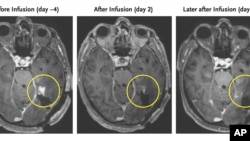

This combination of MRI scan images provided by the New England Journal of Medicine in March 2024 shows the progress of a glioblastoma patient who received CAR-T therapy which uses modified versions of T cells from a patient's own immune system. (NEJM via AP)

Massachusetts General Hospital tested three patients with its CAR-TEAM therapy. Brain imagining a day or two later showed their tumors were quickly becoming smaller. The researchers reported their findings in the publication the New England Journal of Medicine.

Two of the patients’ tumors began to regrow soon. A second treatment given to one of them did not work. But one patient’s response to the experimental treatment lasted more than six months.